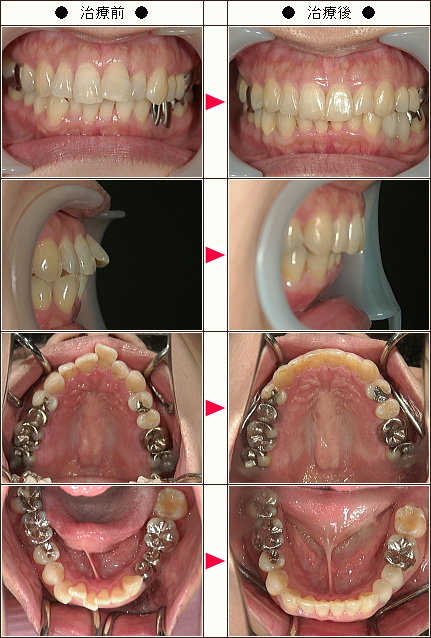

☆歯のデコボコ矯正症例[Y.O.様 40歳 女性]